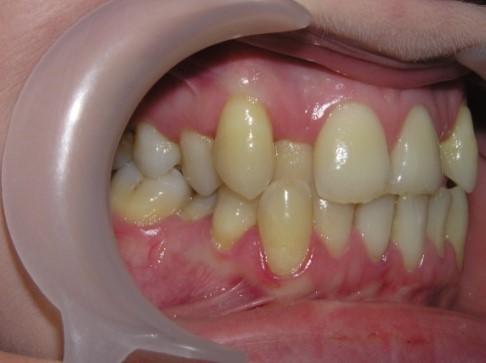

palatal location of the upper jaw incisors, flattening of the frontal area of

the upper jaw and lengthening of the frontal area of the lower jaw are

determined. In this case, exposure of the necks of the lower frontal teeth,

violation of their stability and inflammation of the gums may be observed, and

the clinic of catarrhal or atrophic gingivitis develops as a result of

functional trauma.